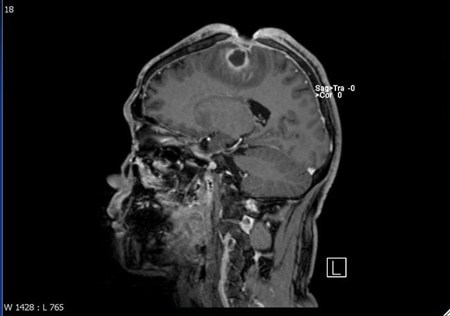

結果陳先生竟然在自己的腦袋挖出5×3×2公分的傷口,這一年期間,他生活、上班一切都沒有異狀,只是習慣用戴帽子的方式將傷口遮住,所以家人同事都沒有發現異狀,結果因為傷口感染,出現類似中風的狀況,家人在協助送醫之後,才知道陳先生竟然將自己的頭骨,腦膜都給挖破了。

傷口因為感染嚴重,醫生除了使用抗生素治療了3個月,還進行清瘡和顱骨重建手術,潘建志表示,這類患者在治療時必須先建立雙方信任關係,才能說服病人進一步治療。病人也因為腦部感染的後遺症,導致右側肢體無力,而復健長達半年的時間。